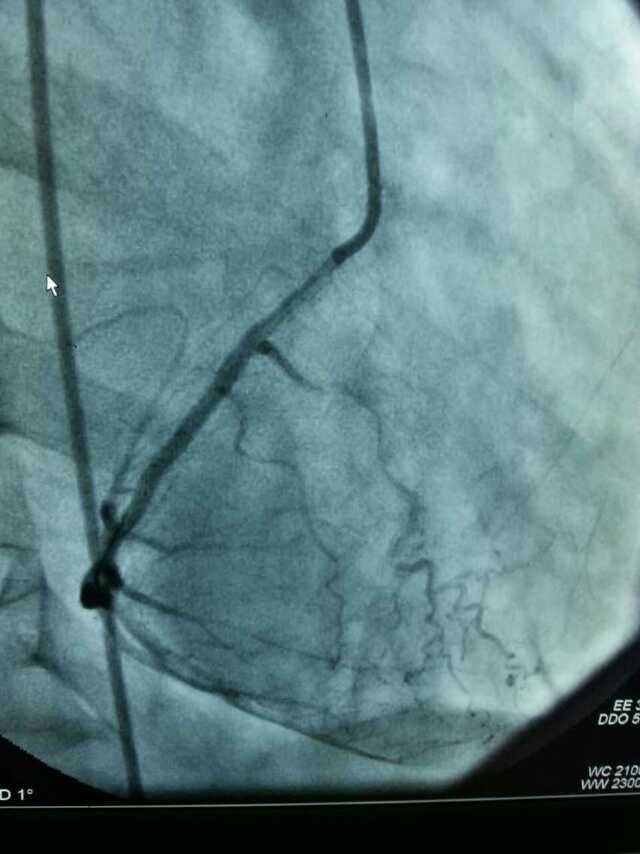

3月20日,家住翔安的庄先生为感谢伦理片 心血管内科的医护人员在第一时间对他的病情给予明确诊断,并及时采取有效治疗措施,让他的心脏病很快得到康复回家。特地送来一面写着“德医双馨,妙手回春”锦旗以表达他们满满的感激之情。